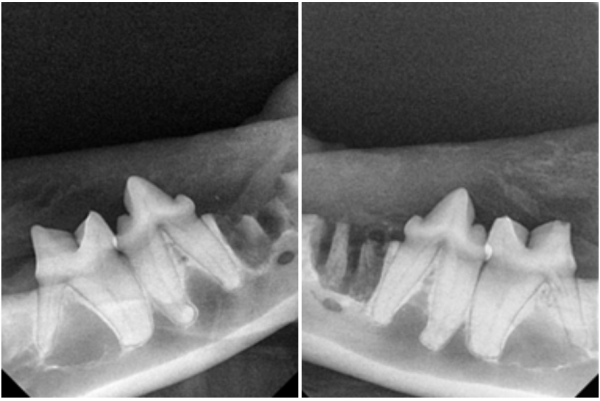

→ 치과 방사선에서도 뚜렷하게

307번의 치아흡수병변이 확인됩니다.

치아흡수병변의 확진은 치과방사선으로 확인합니다.

확인 결과, 방사선상 흡수병변이 발견되었습니다.

만약 치과 방사선을 찍지 않았다면,

407번 치아의 지속적인

통증에 시달렸을 것입니다.

→ 문제가 있었던 307번과 407번 치아는

surgical bur를 이용해 절삭 후

발치를 진행했습니다.